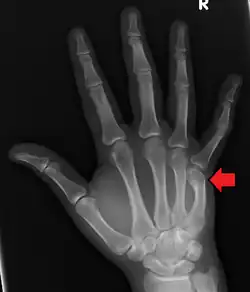

| Boxer's fracture of the 5th metacarpal head from punching a wall | |

A boxer's fracture is the break of the fifth metacarpal bone of the hand near the knuckle.[4] Occasionally, it is used to refer to fractures of the fourth metacarpal as well.[1] Symptoms include pain and a depressed knuckle.[2]

Classically, it occurs after a person hits an object with a closed fist.[3] The knuckle is then bent towards the palm of the hand.[3] Diagnosis is generally suspected based on symptoms and confirmed with X-rays.[3]

Diagnosis by a doctor's examination is the most common, often confirmed by x-rays. X-ray is used to display the fracture and the angulations of the fracture. A CT scan may be done in very rare cases to provide a more detailed picture.